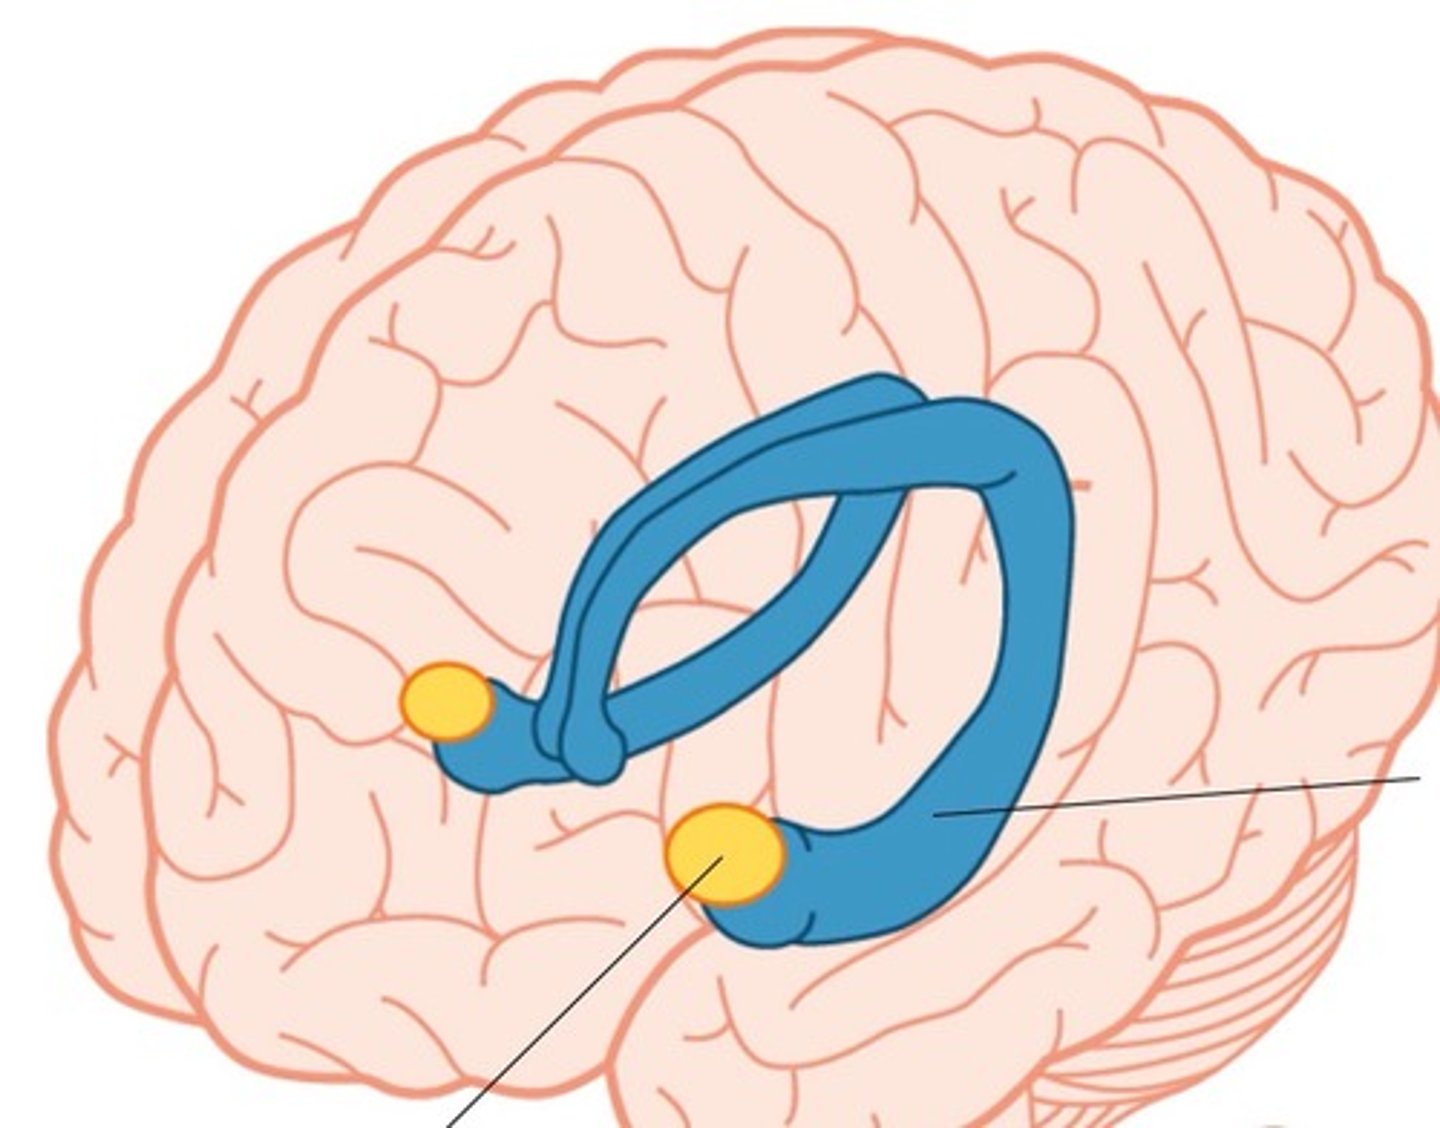

limbic system

a rung of structures that encircles the upper part of the brainstem & corpus callosum inside of the cerebrum & floor of diencephalon

limbic lobes

a rim of cerebral cortex on medial surface of each hemisphere. includes cingulate gyrus & parahippocampal gyrus

dentate gyrus

lies between the hippocampus and parahippocampal gyrus

amygdala

lies close to caudate nucleus - responsible for emotions

septal nuclei

located inferior ro corpus callosum

mammillary bodies

lies close to the midline near cerebral peduncles. associated with recollective memory